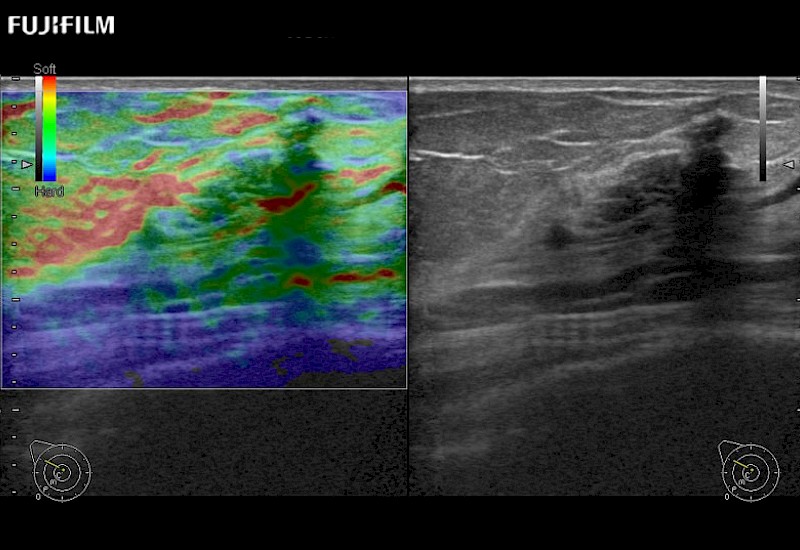

The ARIETTA 750 incorporates all of the proven technologies and functions that medical professionals have come to expect from Fujifilm Healthcare.

ARIETTA 750 is the definitive diagnostic ultrasound solution for any clinical setting - Private Office, Imaging Center, or Hospital. The ARIETTA platform provides the ultimate in clinical performance with its state-of-the-art features and large user-friendly display.

The ARIETTA 650 DI combines trusted Fujifilm Healthcare technologies and features tailored for surgical oncology.

Designed to meet the demands of surgeons, the ARIETTA 650 DI offers precise guidance. Its advanced capabilities and large, intuitive display offer accurate and efficient care in operating rooms and specialized surgical settings.